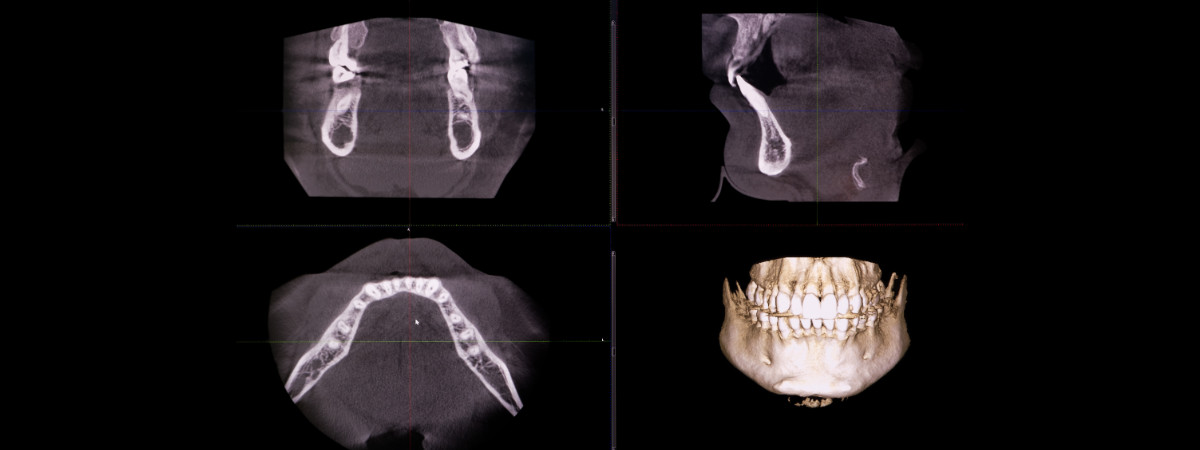

La TAC dentale 3D (Tomografia Assiale Computerizzata) dei denti e delle mascelle è una rappresentazione tridimensionale delle strutture ossee mascellari, che consente un’analisi dettagliata e una pianificazione precisa degli interventi odontoiatrici, come l’inserimento di impianti.

Il CBCT dentale utilizza raggi X per creare una rappresentazione tridimensionale estremamente dettagliata delle strutture del cavo orale. Questa tecnologia consente di visualizzare con precisione ossa, denti, seni paranasali, nervi, tessuti molli e altre strutture anatomiche. Il risultato è un’immagine completa che facilita l’individuazione delle problematiche e la pianificazione mirata dei trattamenti.

La CBCT dentale registra la forma, la posizione e il numero delle radici dei denti. Oltre ai denti, l’immagine mostra anche lo spessore e la densità dell’osso, la posizione del nervo e il seno mascellare in relazione ai denti.

È molto importante sottolineare che queste immagini permettono di identificare eventuali alterazioni patologiche come cisti dentali, granulomi o infiammazioni del dente.